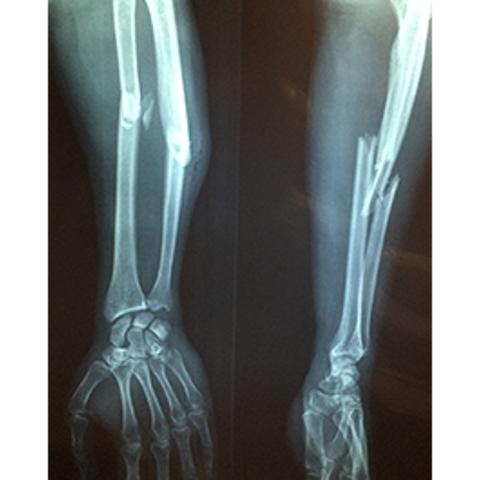

De tyska forskarna hänvisar till flera undersökningar som har visat att typ 1-diabetiker har en försämrad bentäthet vilket gör skelettet skört och att läkningsprocessen tar längre tid. Långvariga höga blodsocker försämrar bentätheten.

De påpekar också att frakturrisken är högre bland typ 1- än bland typ 2-diabetiker. Till exempel är höftfrakturer fem gånger vanligare bland typ 1-diabetiker.